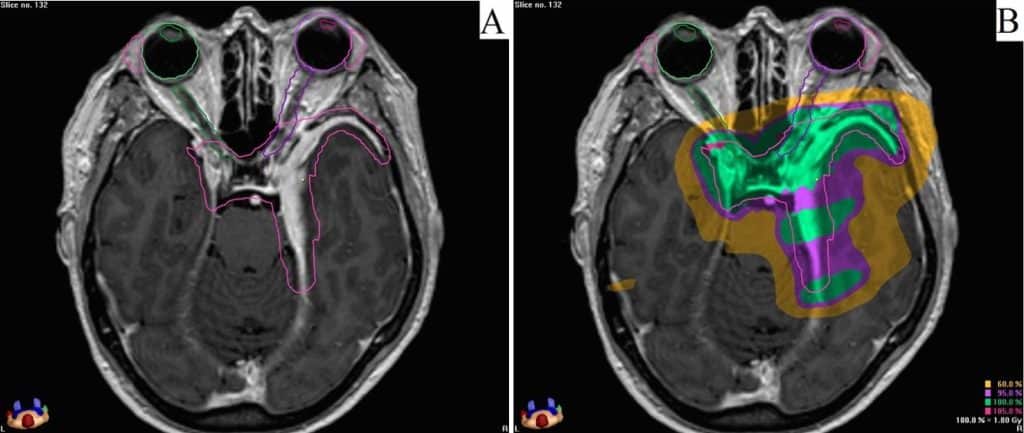

Para meningiomas graus II ou III, indica-se a radioterapia fracionada como forma complementar de tratamento após a cirurgia. Nessa modalidade, a radiação é aplicada em 20-30 sessões diárias, a fim de se evitar a recorrência tumoral.

Radioterapia para meningioma extenso na base do crânio.